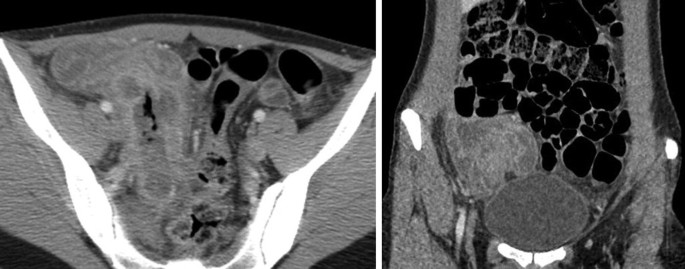

Abdominal Ct Scan Showing Interstitial Edema Of The Pancreas With The Download Scientific Diagram